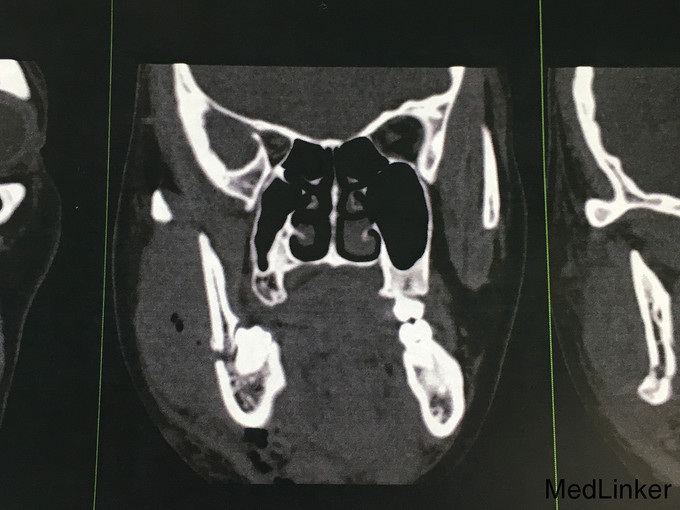

查体:神志清楚,右下颌体部见长约2.0cm开放创口,张口度1.5cm,咬合关系紊乱,右下唇麻木感,43,44间见明显骨折线,异常动度,48松动II,牙龈撕裂,右下颌肿胀,右侧髁状突冲击试验减弱,上颌骨无异常动度,于无异常。 辅查:CT,右下颌骨颏部及下颌角不骨折。

诊断:右下颌骨颏部及下颌角不骨折 治疗:右下颌骨颏部及下颌角部骨折经口内切开复位内固定。